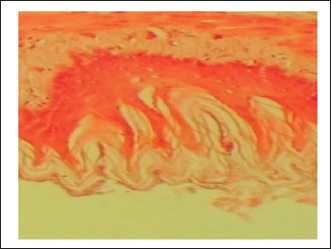

The gastric tissue slides were examined under a microscope for morphological changes such as hyperemia, hemorrhage, edema, necrosis, inflammatory changes, distortion, erosion, and ulcers caused by the destructive effects of indomethacin on stomach tissues. No pathological changes were observed in the normal control group (Fig. 1). Rats in the ulcer control group showed significant damage to the surface epithelium, necrotic areas penetrating the mucosal layer, and severe edema of the submucosal layer. Additionally, there was congestion with infiltration of inflammatory cells (Fig. 2). Histological results revealed that the treated rats with ranitidine had less protection of the gastric lining due to mild infiltration of leucocyte and edema in the submucosal layer, in addition to less disruption in both the superficial and deep mucosal layers. Treatment doses (300, 400 and 500 mg/kg) with P. farcta extract. Groups treated with P. farcta extract (300 and 400 mg/ kg) showed mild infiltration of inflammatory cells, edema, or significant disruption of the deep mucosa (Figs 5 and 6) while, P. farcta extract group (500mg/ kg) prevented histological changes and showed no infiltration of inflammatory cells, edema, or significant disruption of the deep mucosa (Figs 3, 4 and 7).

Fig. 1. Gastric mucosa lesion in rats; G1 served as control group; G2 served as ulcer control with indomethacin have sever injuries; G3, G4 and G5 received extract of Prosopis farcta at 300,400 and 500 mg/kg; G6 served as standard control with Ranitidine.

Fig. 3. Ulcer control group damage (↗) to the epithelium, necrotic areas penetrating the mucosal layer, and (↗) severe edema of the sub-mucosal layer with congestion and (↗) infiltration of inflammatory cells

Fig. 5. Prosopis farcta extract (300mg/kg) mild (↗) filtration of inflammatory cell, (↗) edema or less (↗) disruption in both the superficial and deep mucosal layers

Fig. 6. Prosopis farcta extract (400mg/kg) mild (↗) filtration of inflammatory cell, (↗) edema or less (↗) disruption in both the superficial and deep mucosal layers

Fig. 7. Prosopis farcta extract (500 mg/kg) prevented histological changes, nofiltration of inflammatory cells, edema, or distruption of deepmucosa.